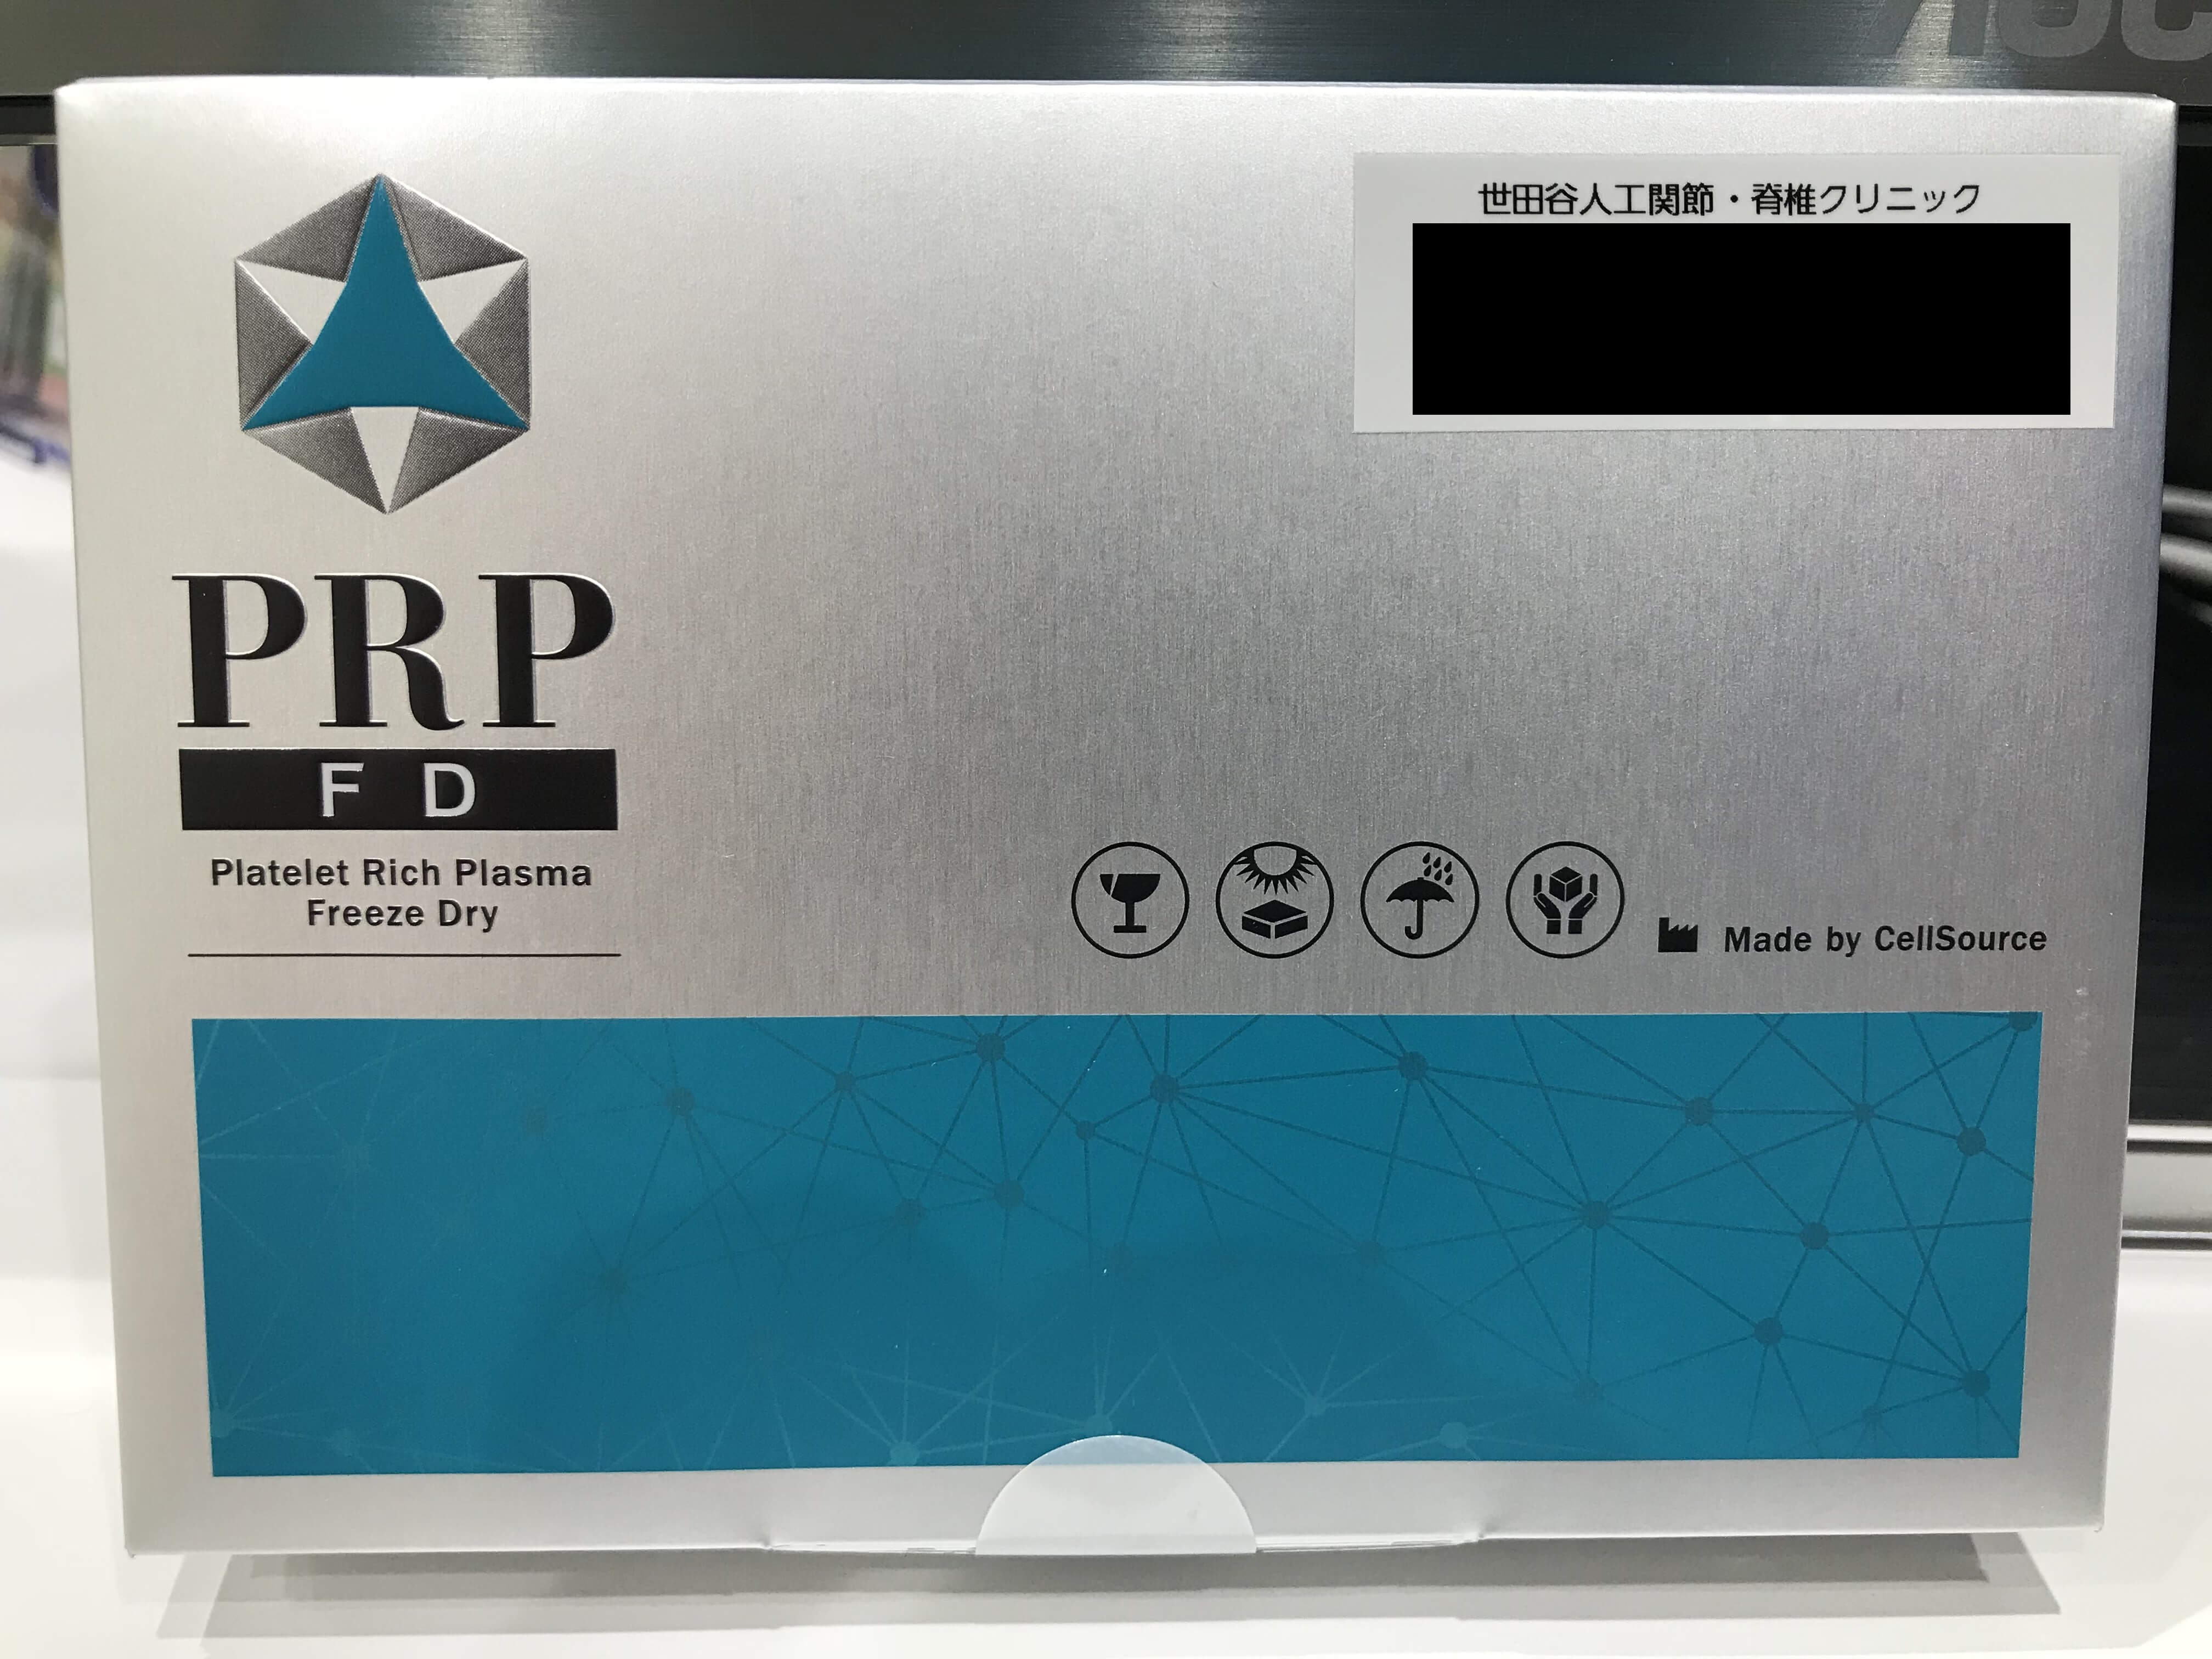

当院では再生医療の治療の選択肢として

APS療法の注射を行っています。